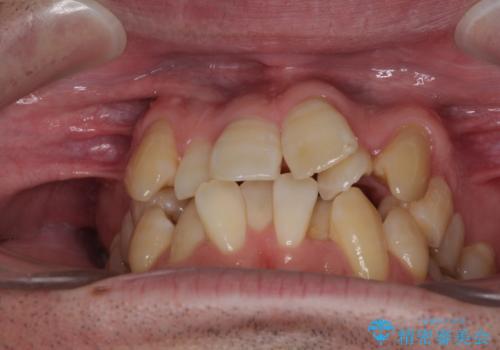

- 前歯のデコボコを気にして来院された患者様です。

叢生の解消とともに、前方に張り出した上顎前歯を引っ込めることを目的とし、上下左右の第一小臼歯4歯を抜歯をしてワイヤー矯正により治療することとしました。